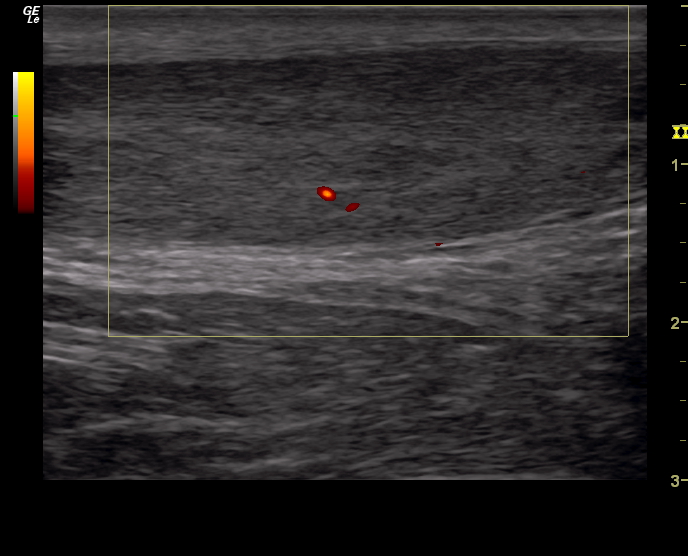

Гипертиреоз узи

Гипертиреоз узи 110 фото